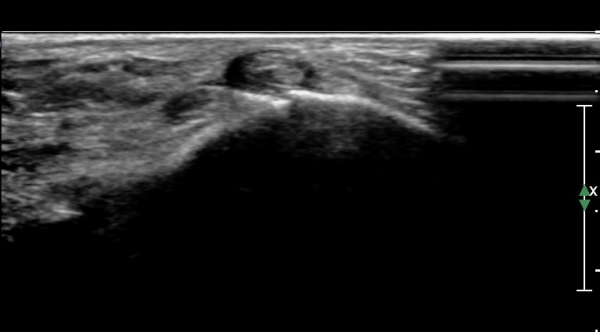

ÃÊÀ½ÆÄ°Ë»ç : ¹ß¸ñ °üÀý Á¾´Ü¸é°Ë»ç¿¡¼­ ¹ß¸ñ °Å°ñ ¿¬°ñÀÌ ¾ã¾îÁ®(thinning) º¸ÀδÙ(»çÁø 1).